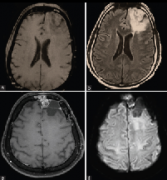

額葉膠質瘤手術是什么樣的?全程簡述

額葉膠質瘤手術是什么樣的?全程簡述無對比:注意瘤周區(qū)域的密度和鈣化;低密度與低級別膠質瘤相關;將這些膠片與對比的計算機斷層掃描進行比較   對比:注意增強程度;低級...